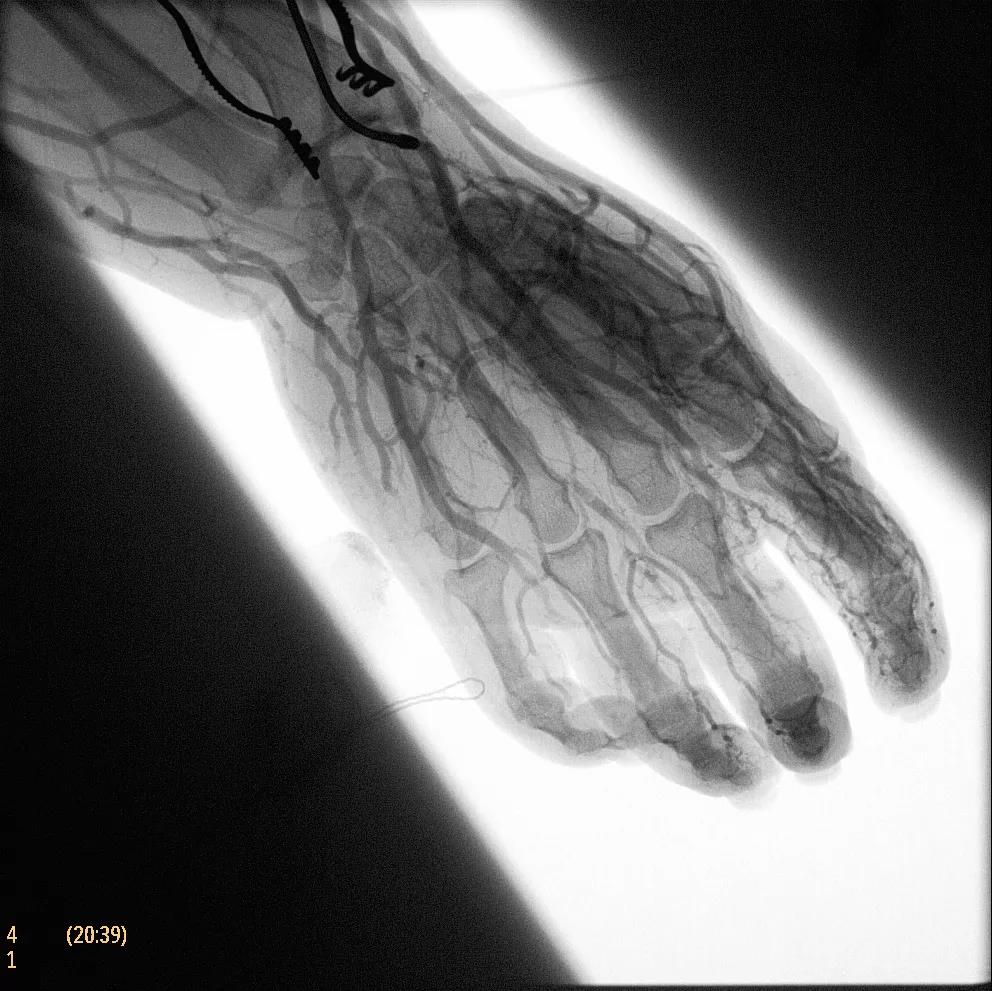

為了獲得清晰的高質(zhì)量圖像,Zenition 70 采用了與公司Azurion平臺相同的圖像處理算法,可提供患者解剖結(jié)構(gòu)的高清可視化和更大的可視區(qū)域。飛利浦的MetalSmart軟件等功能可確保圖像質(zhì)量,該軟件可自動調(diào)整圖像的對比度和亮度,以便在視野中存在金屬物體(如植入物)時提高圖像質(zhì)量 - 這一特性使Zenition 70在整形外科中特別有用。